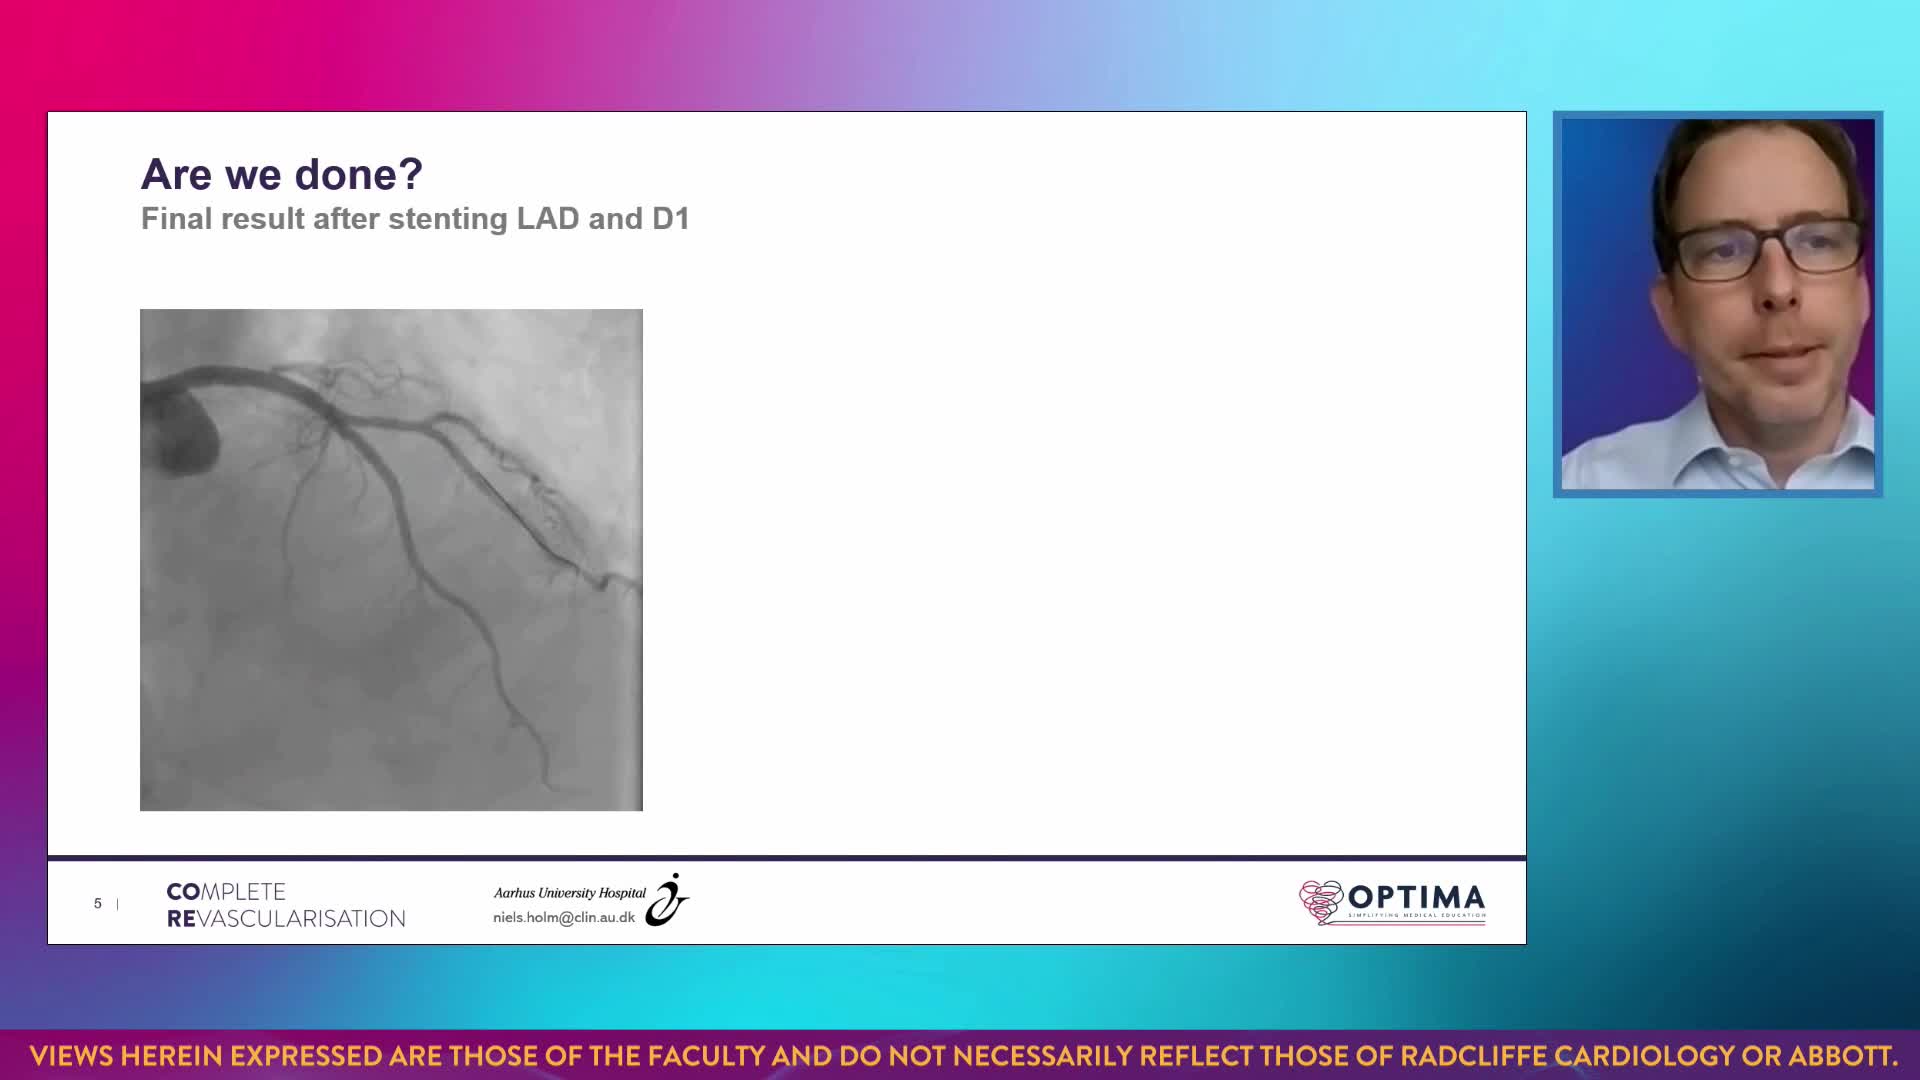

The integrated use of physiology and imaging is transforming the treatment of complex bifurcation disease. We explore...